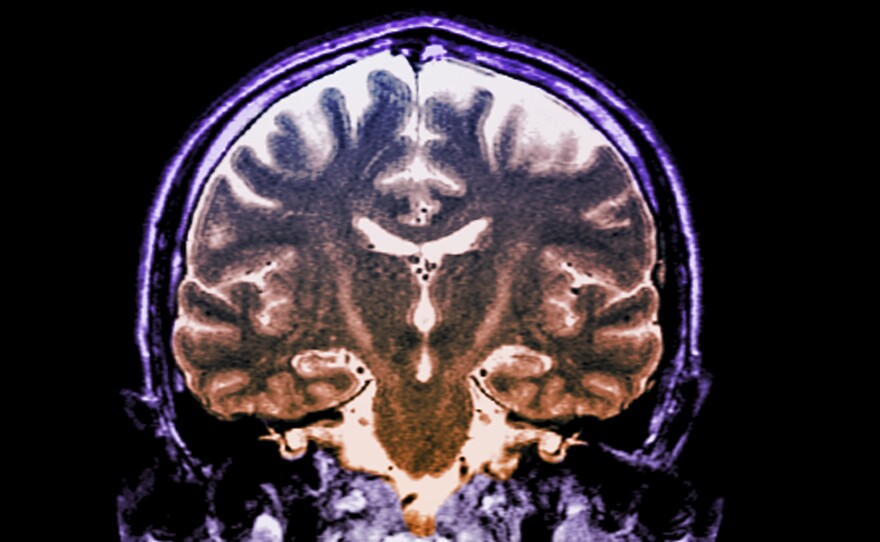

Patients with a fast-progressing form of ALS who got daily doses of an experimental two-drug combination called AMX0035 scored higher on a standard measure of disability than patients who didn't get the drug.

Zephyr / Science Source